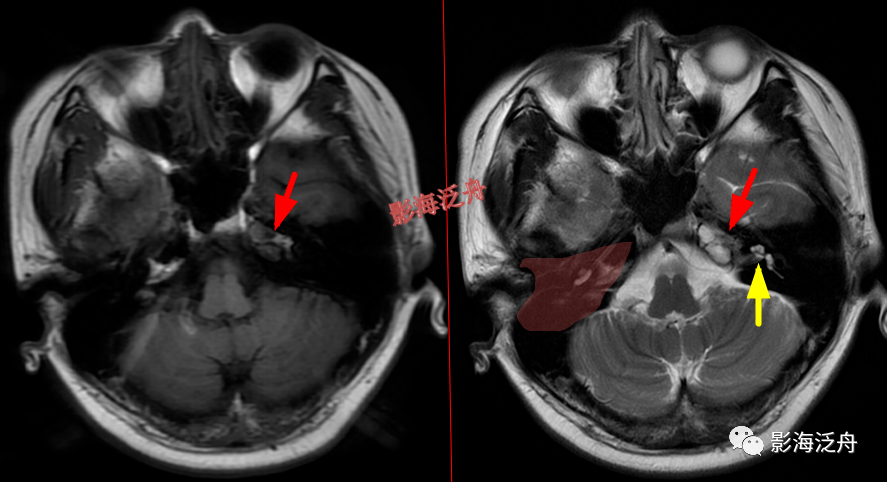

鉴别诊断丨桥前池肿块

颅骨病变脑膜炎患者,桥前池内可见异常增多的血管影(红箭),正常人的桥

本例桥前池可见囊虫结节,属于蛛网膜下腔型